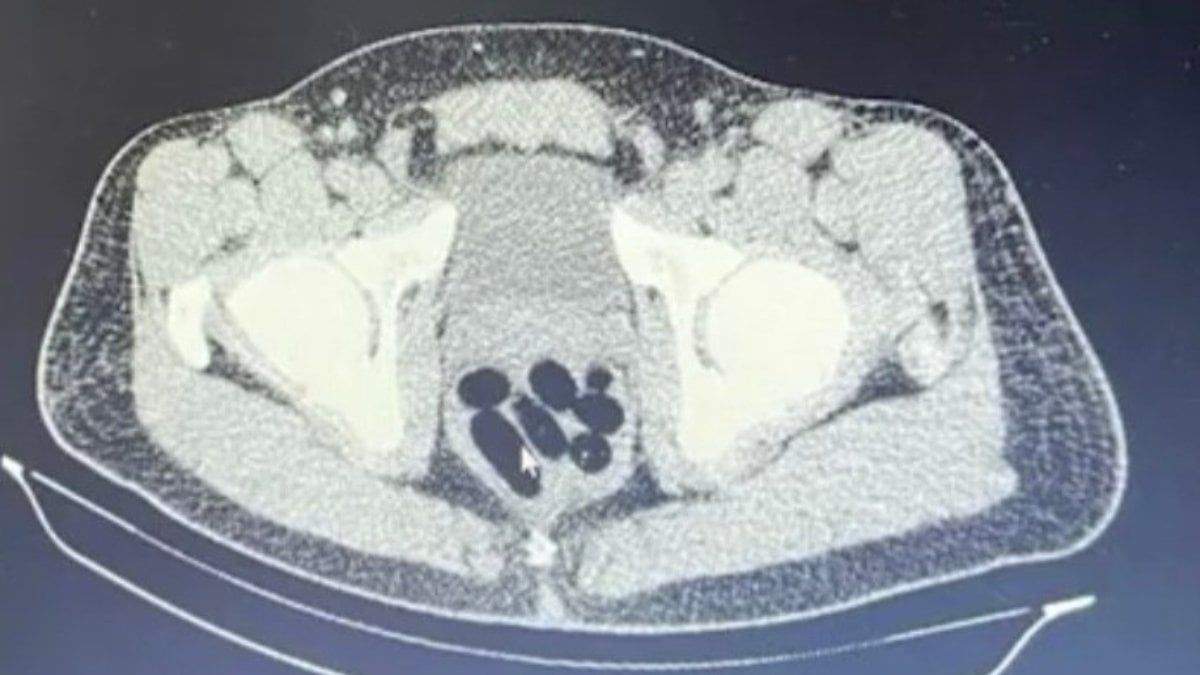

UYUŞTURUCULAR MİDESİNDEN ÇIKTI

Gözaltına alınan şüphelinin hastanedeki iç beden muayenesinde 77 adet kapsül şeklinde 1 kilo 134 gram narkotik madde ele geçirildi.

Şüphelinin midesindeki maddeler cerrahi müdahale ile çıkarılırken hakkında uyuşturucu madde ticareti yapmak suçundan adli işlem başlatıldı.